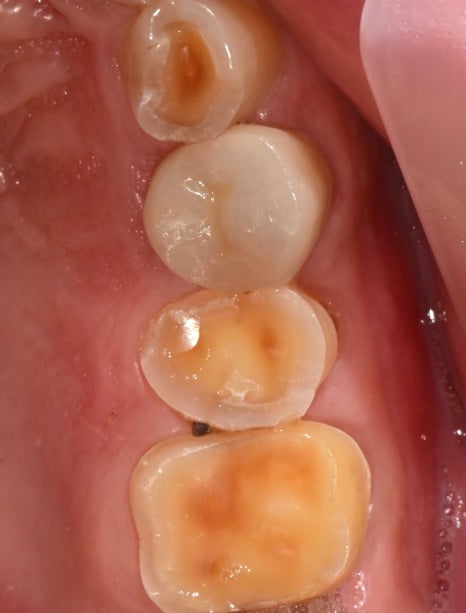

신경치료를 하며 통증 개선 및 증상 체크를 하며 마무리를 하고 보철치료를 통해 치아 외형을 복원하였습니다.

주변 치아가 마모가 심하게 되어있는 상태라 모양이 어색해 보이지만

주변 교합력을 분산시키기 위해 교합조정도 꼼꼼히 진행했습니다.